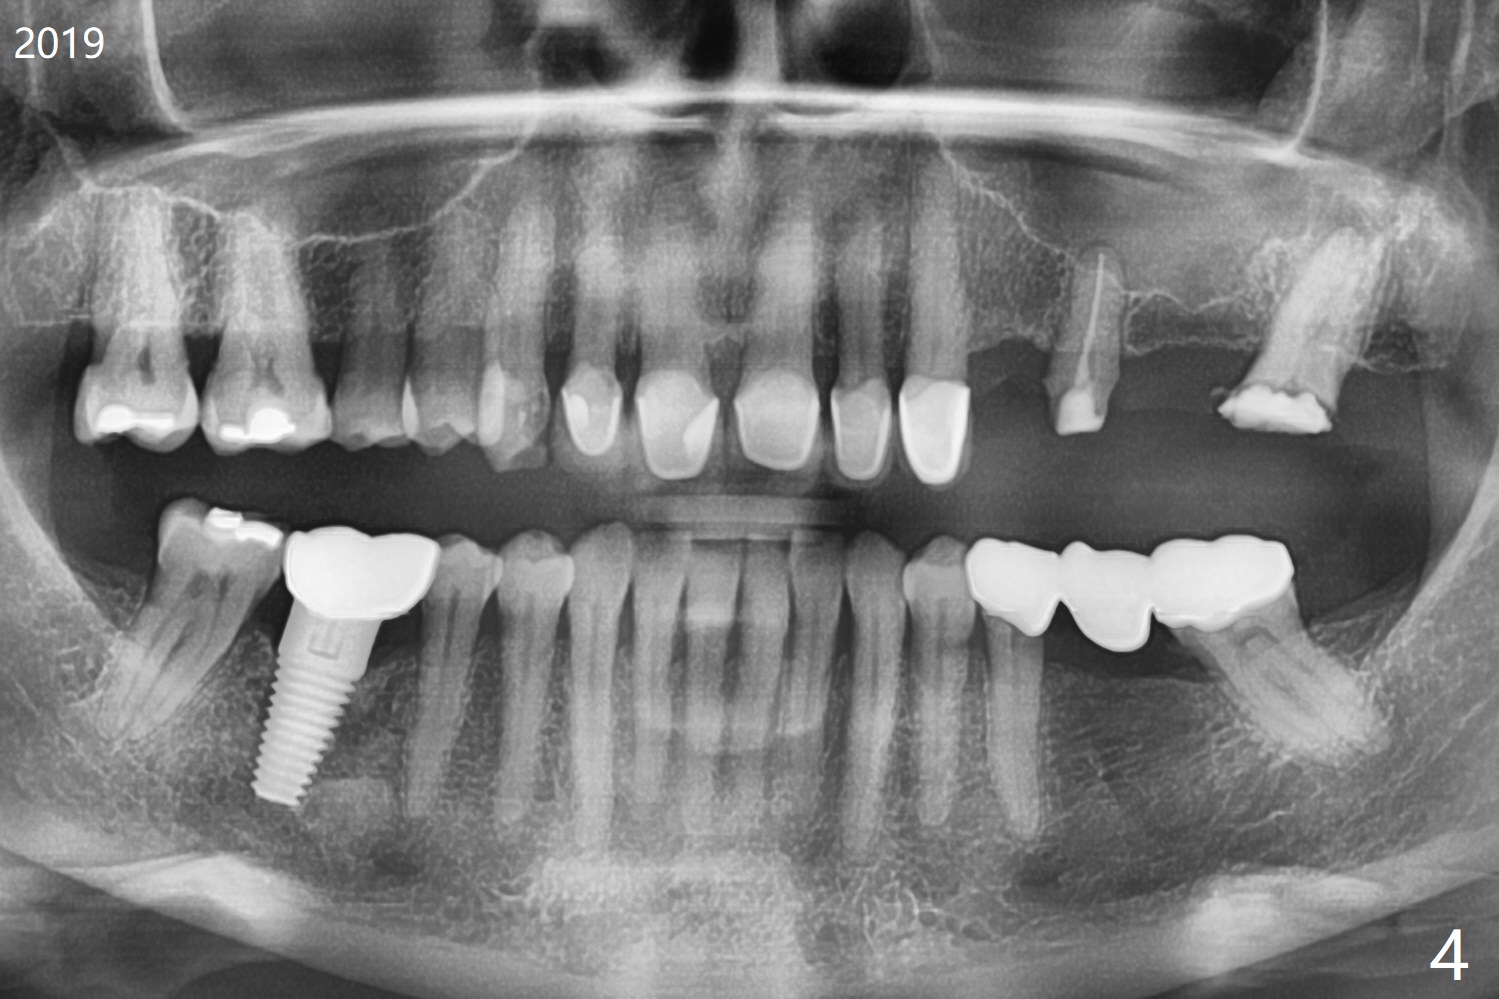

A 55-year-old woman is a bruxer (Fig.1). In 5 years the upper left FPD is fractured between #11 and 12 (Fig.2) and at #15 (Fig.3). Sectioning the FPD shows #15 non-salvageable (Fig.4). Implants will be placed at #12, 14 and 15. Sinus lift seems necessary at #14 (4 mm).